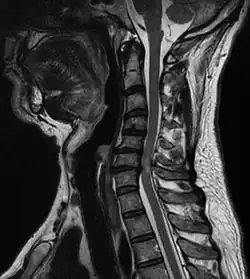

| A tumour causing spinal cord compression | |

Spinal cord compression is a form of myelopathy in which the spinal cord is compressed. Causes can be bone fragments from a vertebral fracture, a tumor, abscess, ruptured intervertebral disc or other lesion.